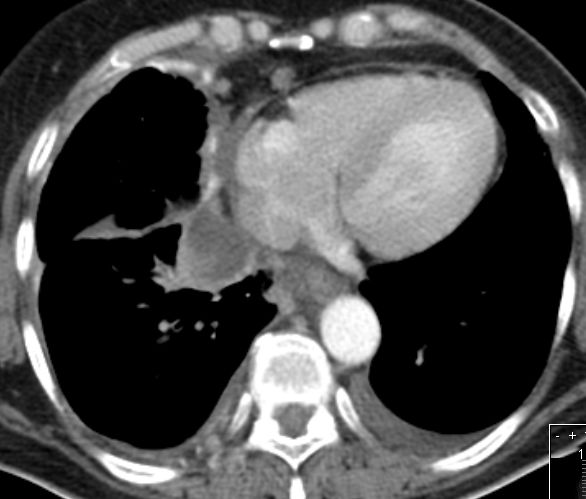

Ascites bei Ovarial - Ca |

Pleuraerguß links bei Ovarial - Ca |

Fortgeschrittenes Ovarialkarzinom mit Ascites und Peritonealkarzinose.![]() | ||